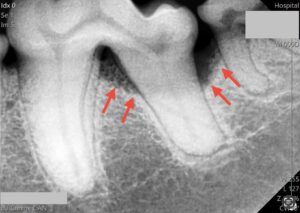

別症例(歯科レントゲンでの比較)

中度歯周病

プロービングを行い、歯周ポケットの有無を確認した後、歯科専用のレントゲンを用いて歯周組織の状態を確認し、必要に応じて抜歯処置もしくはルートプレーニングやキュレッタージにより保存治療を行います。